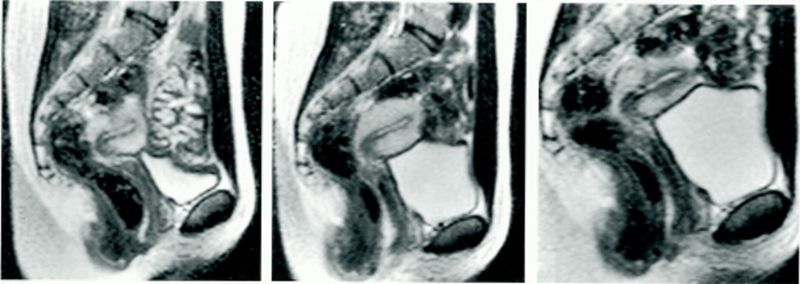

Gambar yang dihasilkan dari pemindaian MRI itu menjadi yang pertama di dunia. Kemudian dipublikasikan dalam artikel ilmiah yang sangat populer di British Medical Journal (BMJ) pada 1999.

Sebuah eksperimen ilmiah yang dilakukan lebih dari tiga dekade kembali menjadi sorotan. Ini terkait apa yang terjadi selama pria dan wanita berhubungan seks. Foto: British Medical Journal (BMJ) |

Sebelumnya, anatomi vagina kerap digambarkan lurus, termasuk dalam ilustrasi terkenal Leonardo da Vinci dari tahun 1492. Itu menunjukkan vagina sebagai silinder lurus.

Namun, hasil MRI menunjukkan penis yang melengkung mengikuti tubuh wanita tanpa menimbulkan rasa sakit pada pria saat ereksi.